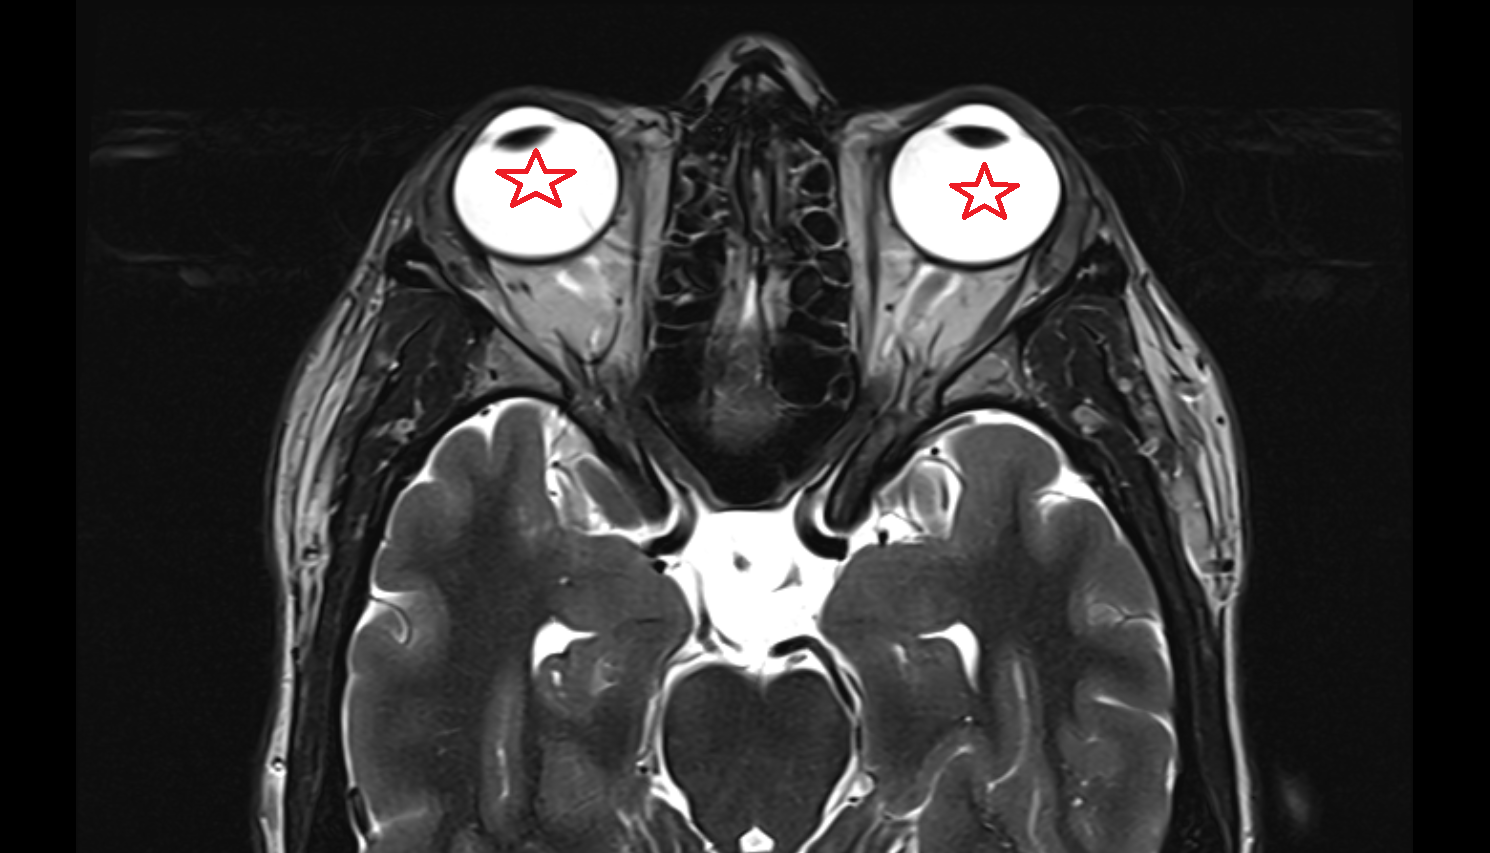

- lens of the eye

- Cornea

- Iris

- Pupil

- Anterior chamber of eyeball

- Posterior chamber of eyeball

- Vitreous chamber of eyeball

- Sclera

- Choroid

- Retina

- Orbital part of optic nerve

- Optic nerve sheath

- Subarachnoid space of optic nerve